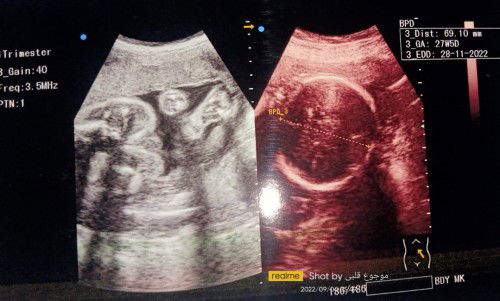

Bayi di kandunganku posisinya miring. Sedangkan usia kandungan udah memasuki 3semester apa bisa nor?

baru 27w5d ya bun? gapapa sih kan baby masih muter².. ruang geraknya masih lumayan luas. dan masih banyak waktu ko bun buat debaynya menyesuaikan diri utk masuk panggul..